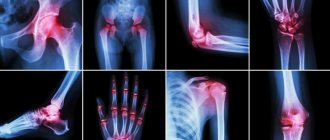

Гомеопатический в/м раствор Убихинон Композитум показан для применения в комплексном лечении при:

• дегенеративных хронических болезненных состояниях внутренних систем и органов;

• синдроме интоксикации (в том числе при инфекционных заболеваниях с лихорадкой, кахексии);

• расстройстве обмена веществ в организме (в том числе подагре, желчно— и почечнокаменной болезни, атеросклерозе);

• относительном или абсолютном дефиците витаминов и/или ферментов;

• состояниях, связанных с гипоксией, по причине различных заболеваний, психического и/или физического стресса;

• последствиях лучевой терапии и/или химиотерапии.